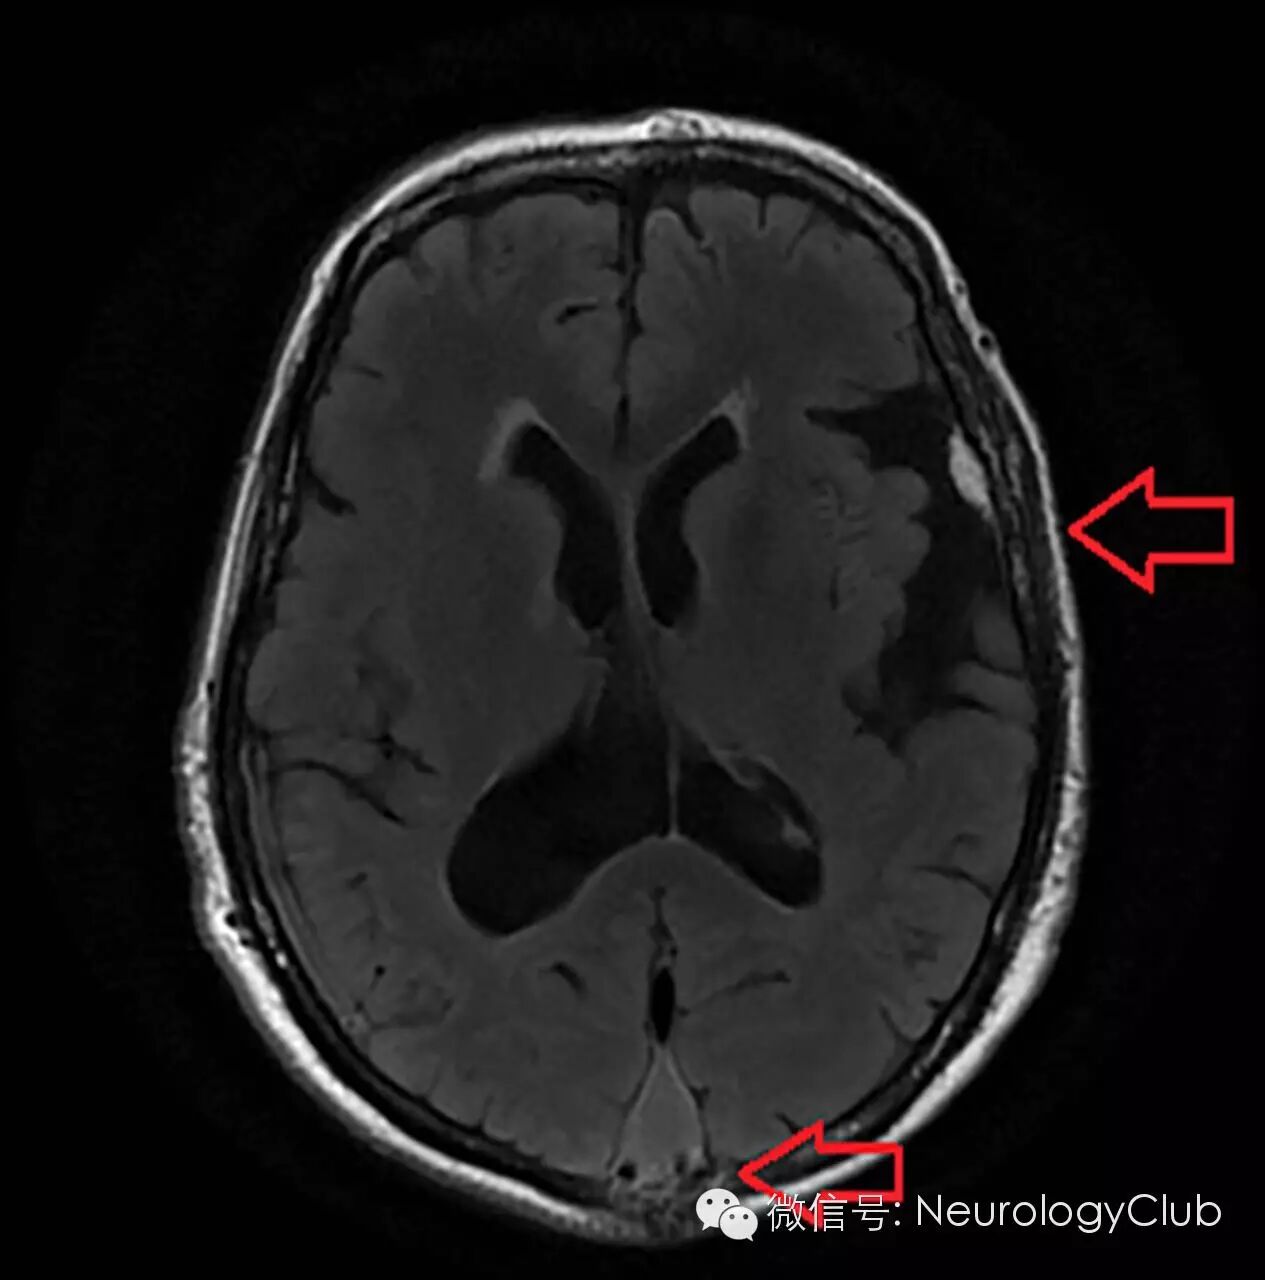

(FLAIR证实左侧海绵状血管瘤[上箭],原来上矢状窦的位置出现异常组织[下箭])